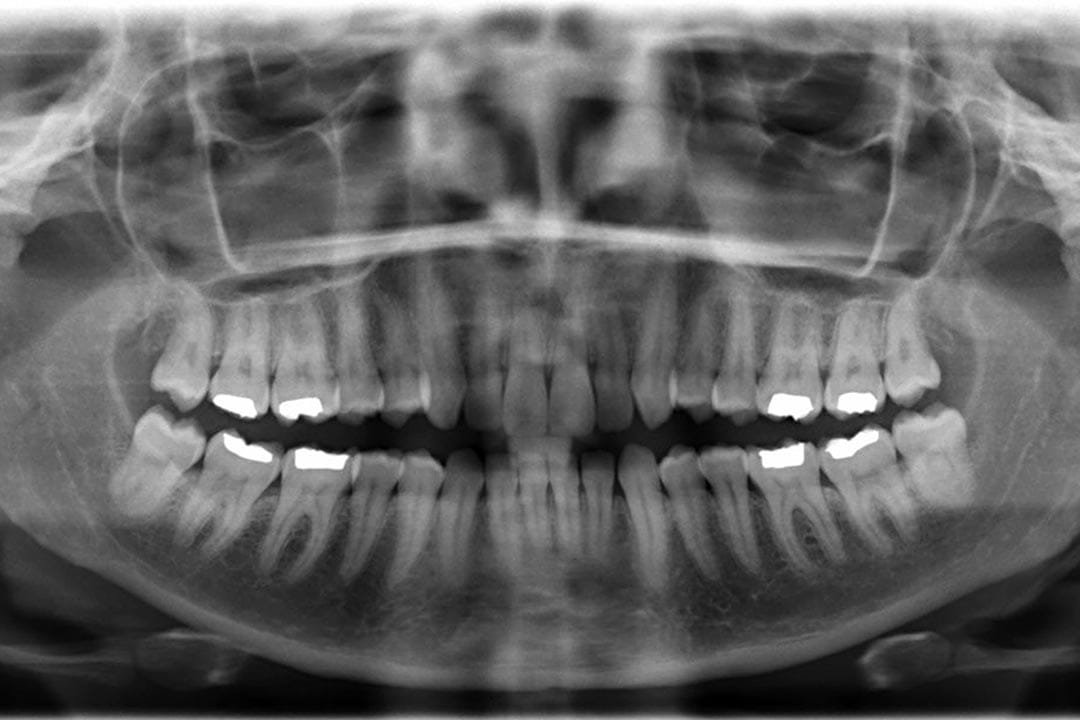

图片由香港马凌画廊提供